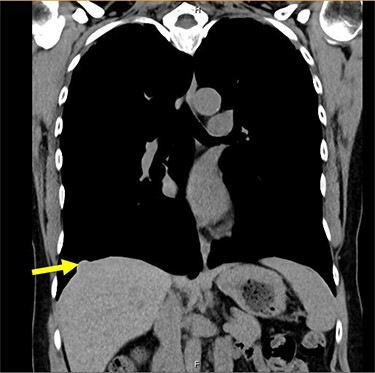

A 54-year-old female without prior thoraco-abdominal trauma presented to the office with two right lower lobe lung nodules. The nodules were initially noted incidentally on a computerized tomography (CT) scan in August 2009 and measured 1.5 cm × 2.8 cm and 0.9 cm × 1.3 cm (Figs 1 and 2). A follow-up CT scan and positron emission tomography (PET) performed in 2010 demonstrated that the nodules were stable in size. The patient was lost to follow-up until March 2019 when she had a CT scan for concern for pneumonia. On these images, the lung nodules had increased in size to 2.8 cm × 4.1 cm and 1.1 cm × 1.4 cm. The patient was otherwise asymptomatic. A PET scan was obtained which showed hypermetabolic nodules with maximum SUV of 3.29 and 1.4, for the larger and smaller nodule, respectively (Figs 3 and 4). Radiographic appearance as well as the growth pattern was consistent with low-grade malignancy suspicious for carcinoid tumor. CT-guided biopsy was not feasible because of location of the tumor.

Liver herniation corresponding to the location of larger lung nodule seen on CT scan.